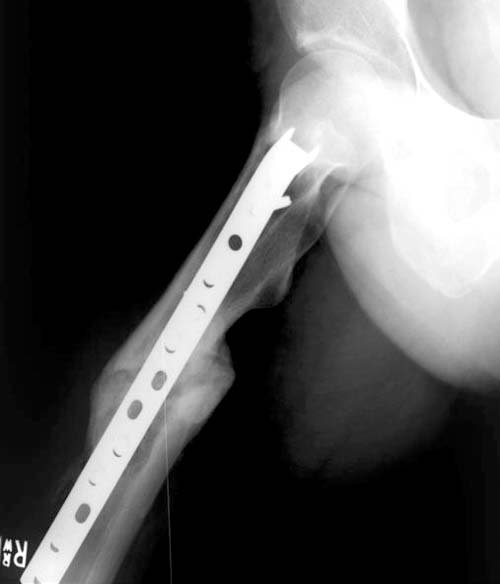

Ув.коллегиОбратился пациент. 55 лет.жалобы на сильные боли в обл нижней трети бедра и колена. Ходит на костылях,практически не приступая на ногу. Оперирован 1 год и 3 мес назад, стержень скорее всего Chm, травма вследствии ДТП.

Думаем,что имеется нестабильность импланта, предлагается перештифтовать на более толстый стержень типа Gamma-long c костной пластикой(?)Хотелось бы услышать мнения коллег . Спасибо, с ув.Тарас Рокита, Киевская гор.больница N7

Мне сдается, что костная пластика здесь не нужна. Причиной несращения, это очевидно, здесь явилась нестабильность (на рентгенограммах очень хорошо виден лизис кости вокруг штифта и винтов в дистальном отломке). С ней, проклятой, и надо бороться.